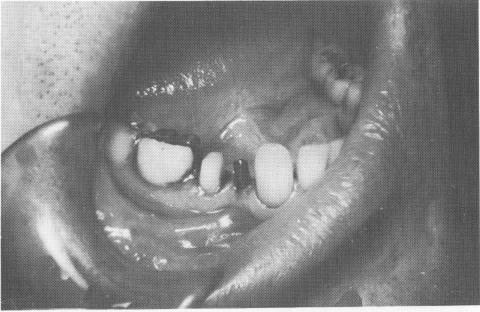

Fig. 8-55. The vent-plant is seen in its proper relationship.

Fig. 8-56. The implant shaft length should not interfere with the occlusal surfaces of the opposing teeth. It should be short enough to allow enough occlusal gold or porcelain to be included in the restoration.

3 Vent plant implant shaft length allows gold, porcelain in restoration